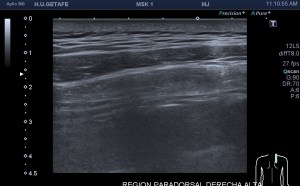

Si colocas la sonda en el mentón, en axial vas a encontrar este músculo Digástrico, que se verá muy bien, superficial, en un plano intermedio tendrás el músculo Milohiodeo y en la profundidad los músculos Geniohideos, Geniogloso y el Hiogloso…Mira:

El Músculo Milohioideo se encuentra en un plano medio, es fino y separa el plano superficial muscular, del profundo, en la imagen superior ves una pequeña porción de este músculo. En el plano profundo un grupo de varios músculos, que he mencionado más arriba y que son músculos extrínsecos de la lengua, situados en la región más medial de esta localización submentoniana estudiada.

Fíjate en esta anatomía cuando estes realizando una exploración de cuello o de tiroides en la búsqueda de quistes del Conducto Tirogloso o de adenopatías.